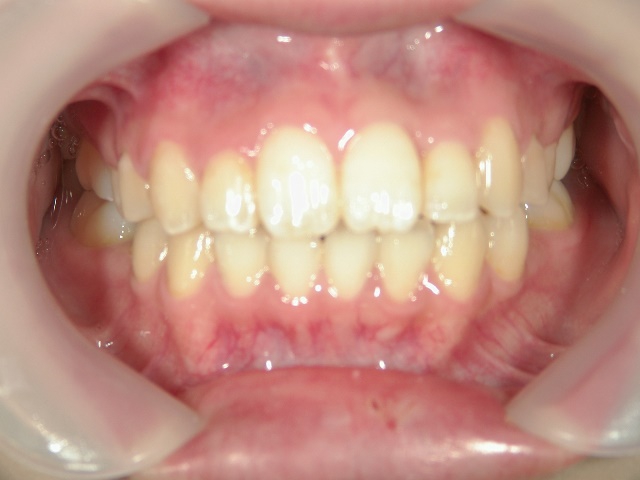

no.8_8495_治療後_左.jpgno.8_8495_治療後_正面.jpgno.8_8495_治療後_右.jpg

矯正歯科 治療後